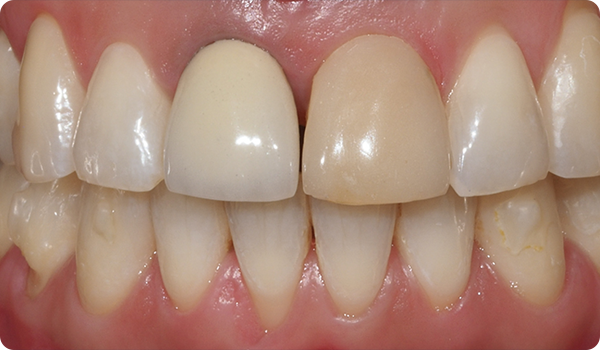

Med Right får dine patienter det smil, de ønsker, inden for den ønskede tid, på en komfortabel og "usynlig" måde.

At justere tænder med Right er den perfekte og mest skånsomme forberedelse til fremtidig tandblegning eller facadebehandlinger, der vil perfektionere patientens smil.